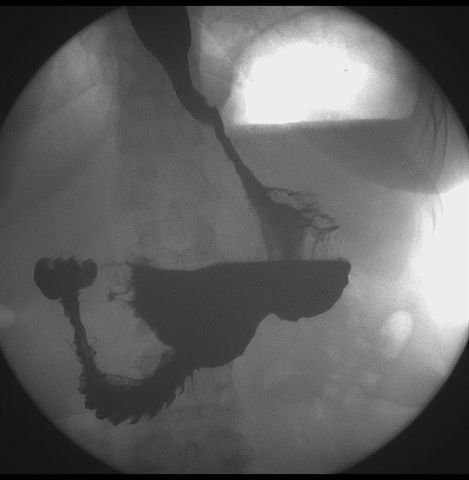

标题: X6872:F,69y,胃部不适。

胃窦至幽门段胃壁僵硬,扩张受限,局部纠集粘破坏,呈杵状。提示溃疡癌变可能性大。

胃窦癌可能性大,建议胃镜活检。钡剂太稀,吃的有点多。

支持考虑胃窦癌可能,胃内滞留液太多,胃窦部僵硬。

胃窦部见钡池影,局部粘膜紊乱,纠集呈杵状改变,胃壁扩张受限,胃窦癌可能性大,建议胃镜检查.

胃窦部管腔扩张度较差,形态略有改变,胃窦粘膜显示欠佳,胃窦部占位可能性大,结合胃镜活检。

胃窦部狭窄、稍僵硬,考虑胃窦癌?建议胃镜检查。

北京肿瘤医院胃镜诊断皮革胃。